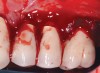

Fig 3. The implants were treated with a Nd:YAG laser. A thrombogenic clot was present at the completion of this treatment.

Figure 3